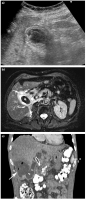

Cholecystis

Abbildung 2a-c: Cholecystitis. (a) Die Sonographie zeigt eine deutlich wandverdickte 3-geschichtete Gallenblase bei akuter Cholecystitis. (b) Die MRT zeigt nicht nur Konkrement (Stern) und die deutlich verdickte Gallenblasenwand, sondern auch einen kleinen intramuralen Abszess (Pfeile). (c) Die kontrastmittelverstärkte MDCT zeigt bei einem anderen Patienten mit schwerer Sepsis eine Perforation (Pfeilspitze) der Gallenblase (G) mit einem großen Leberabszess (Pfeil).

Keywords: CholezystisGastroenterologieHepatologieMDCTMRTSonographie